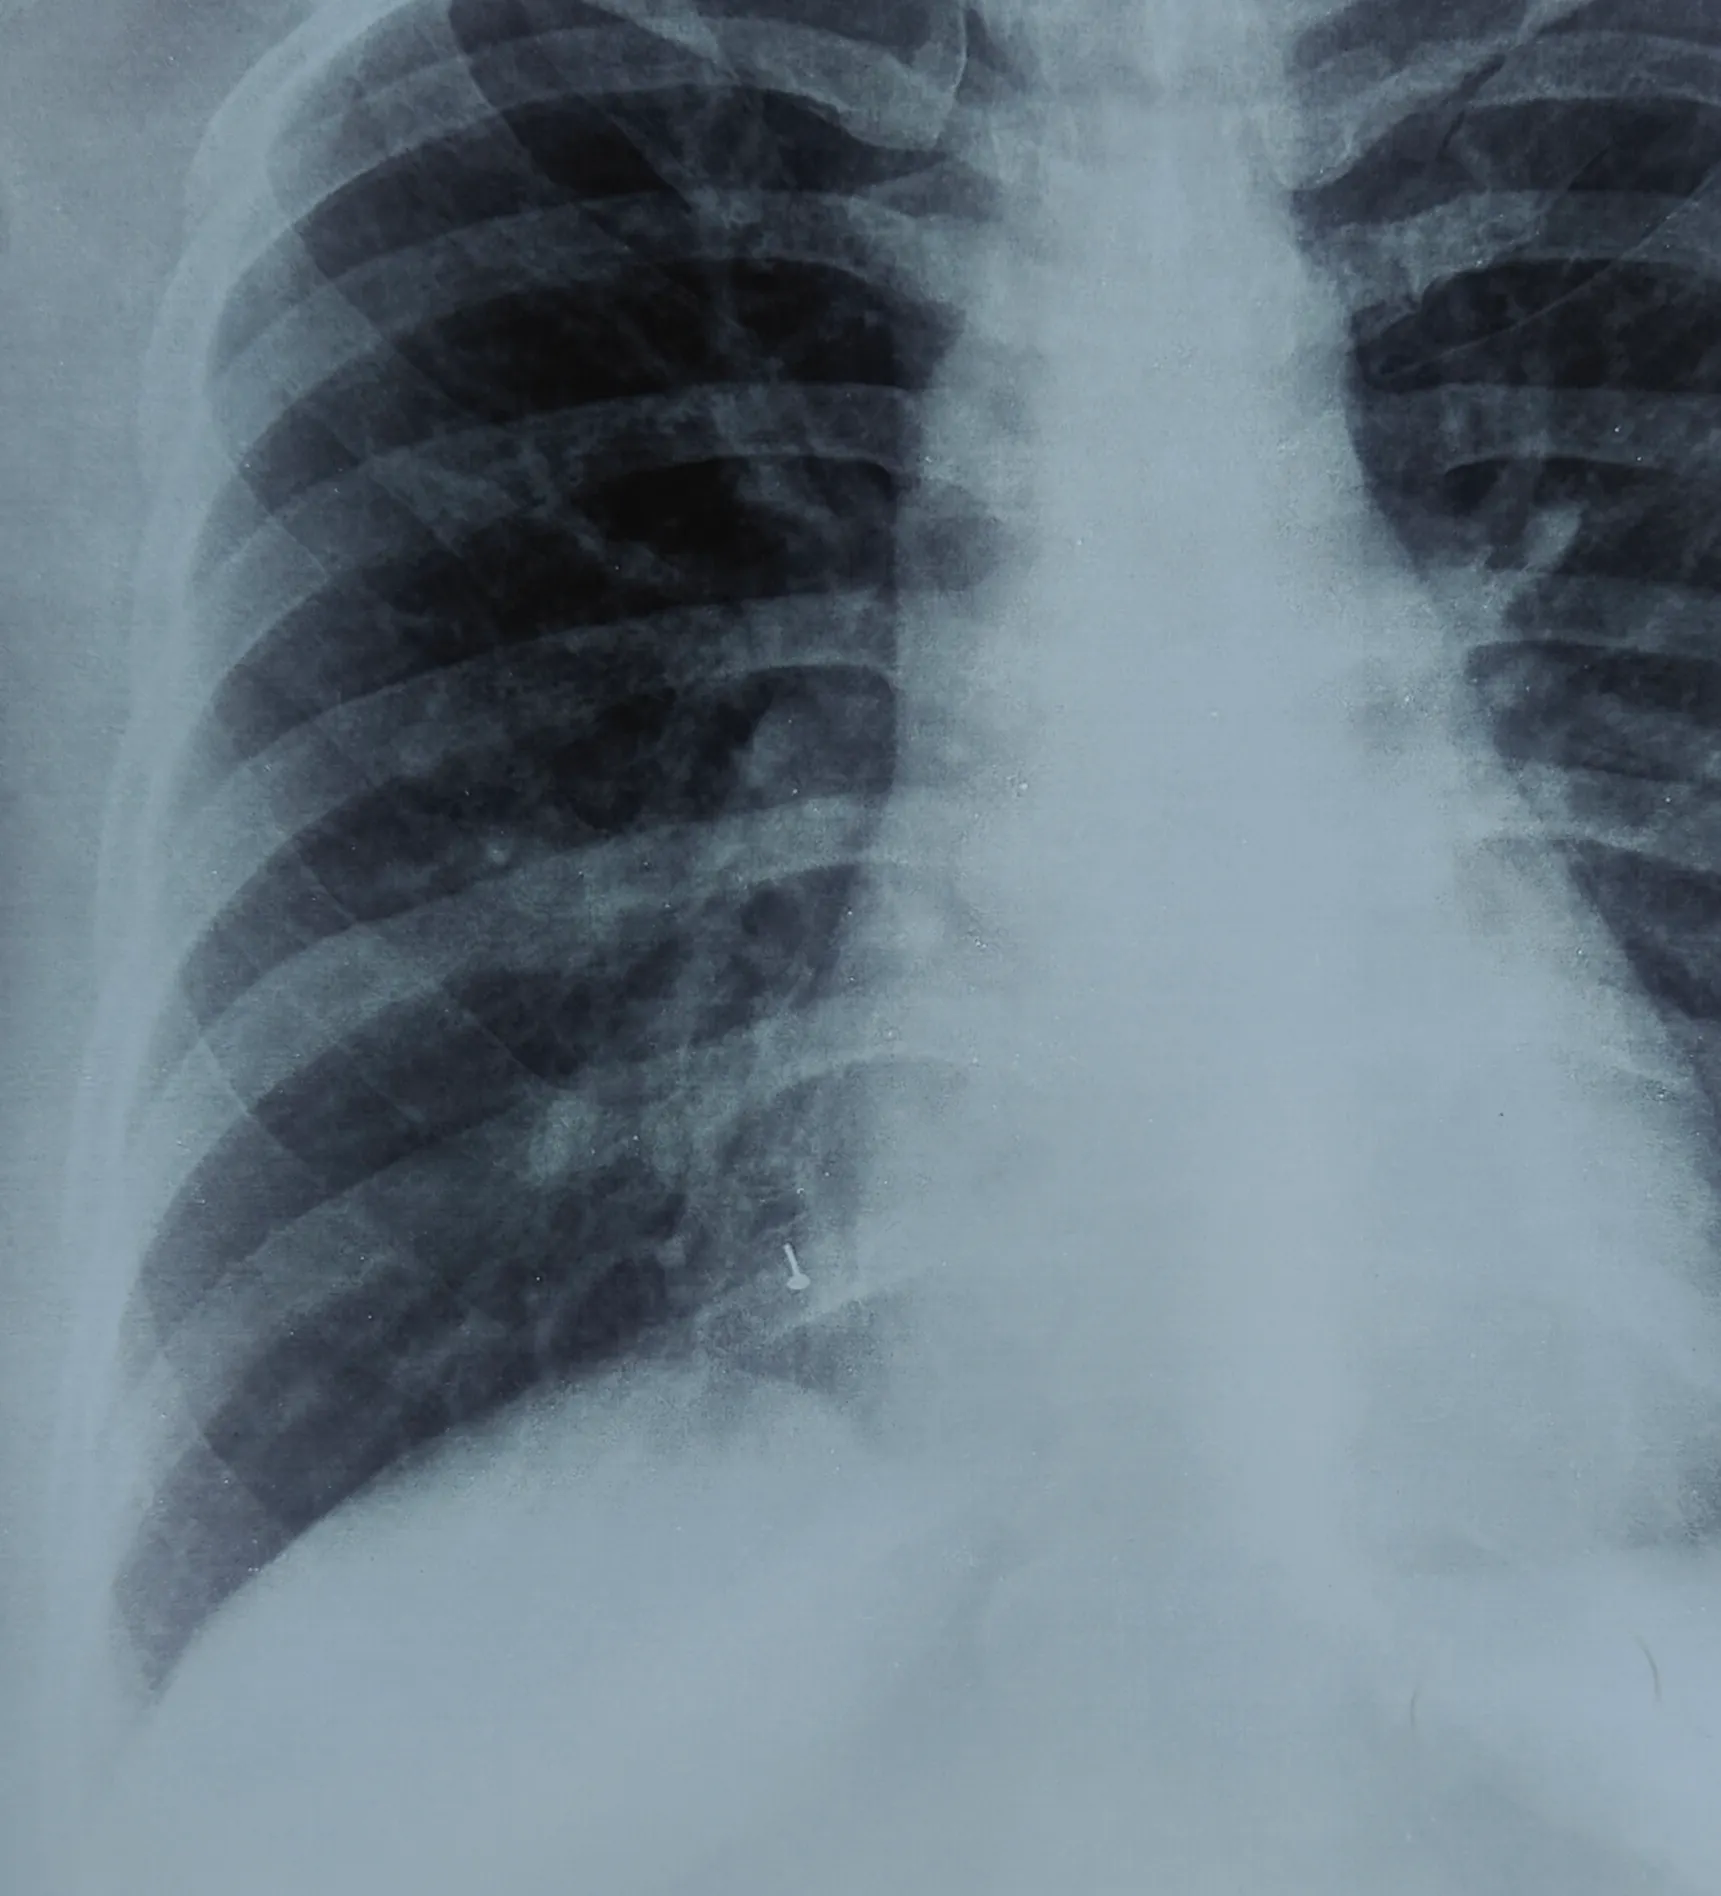

വിട്ടുമാറാത്ത പനിയും ചുമയുമായി കൊച്ചിയിലെ സ്വകാര്യ ആശുപത്രിയില് ചികിത്സ തേടിയപ്പോള് എടുത്ത എക്സ്-റേയിലാണ് നാലുവര്ഷം മുന്പ് കാണാതായ മൂക്കുത്തിയുടെ ചങ്കിരി വലത്തെ ശ്വാസകോശത്തിന്റെ കീഴ്ഭാഗത്ത് തറച്ചിരിക്കുന്നതായി കണ്ടെത്തിയത്. തുടര്ന്നാണ് വിദഗ്ദ ചികിത്സക്കായി രോഗി അമൃത ആശുപത്രിയിലെത്തിയത്.